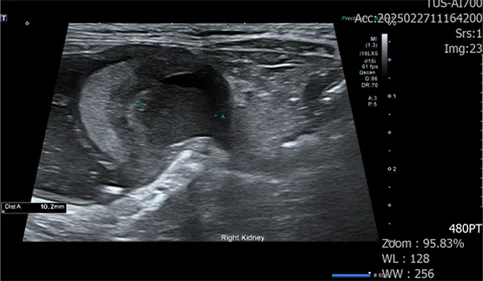

초음파 검사에서는 신장의 피질과 수질이 구분되지 않고, 실질 내 다수의 낭종이 있는 형태학적 변화가 확인되어 유전적 신장 기형 및 만성적인 신장 기능 저하가 있었던 것으로 의심되었습니다.

신우내 저류하는 액체 천자 진행, 점액성 농이 다수 확인

정밀 검사 결과, 신장 주변 가스, 복수, 신장 파열이 확인되었습니다.